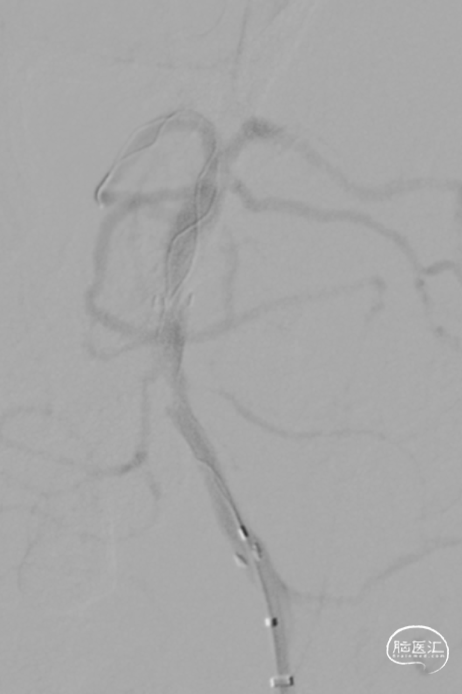

第一次取栓后,血管未通,但明确支架内狭窄位置,交换引入头端塑形的300cm 0.014in微导丝,撤出微导管,沿微导丝引入2.0mm*15mm Sprinter球囊,扩张后狭窄明显减轻,但血栓掉落至右侧大脑后动脉起始部。

交换再次引入加奇4.0mm*30mm Syphonet®取栓支架并释放。

第二次拉栓后造影,血管再通,支架内再狭窄处理风险极高,且目前前向血流3级,对比造影时影像支架未有移位。